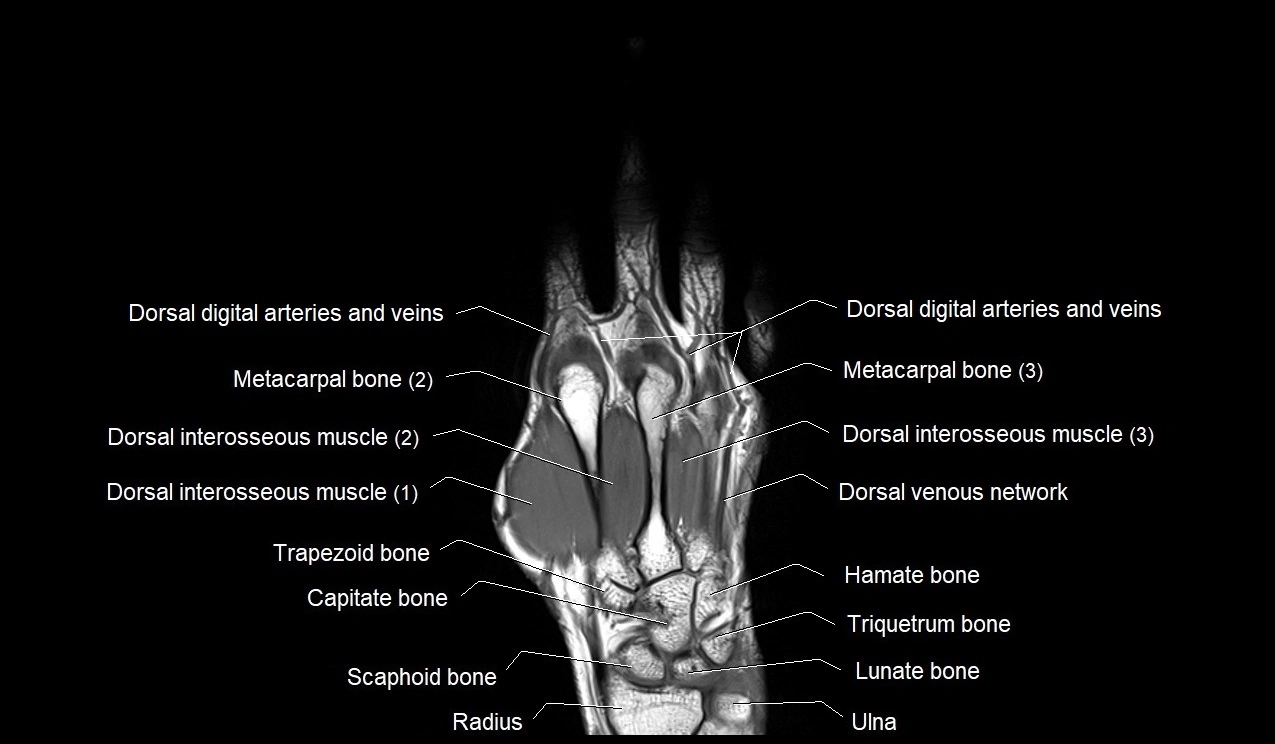

CT image